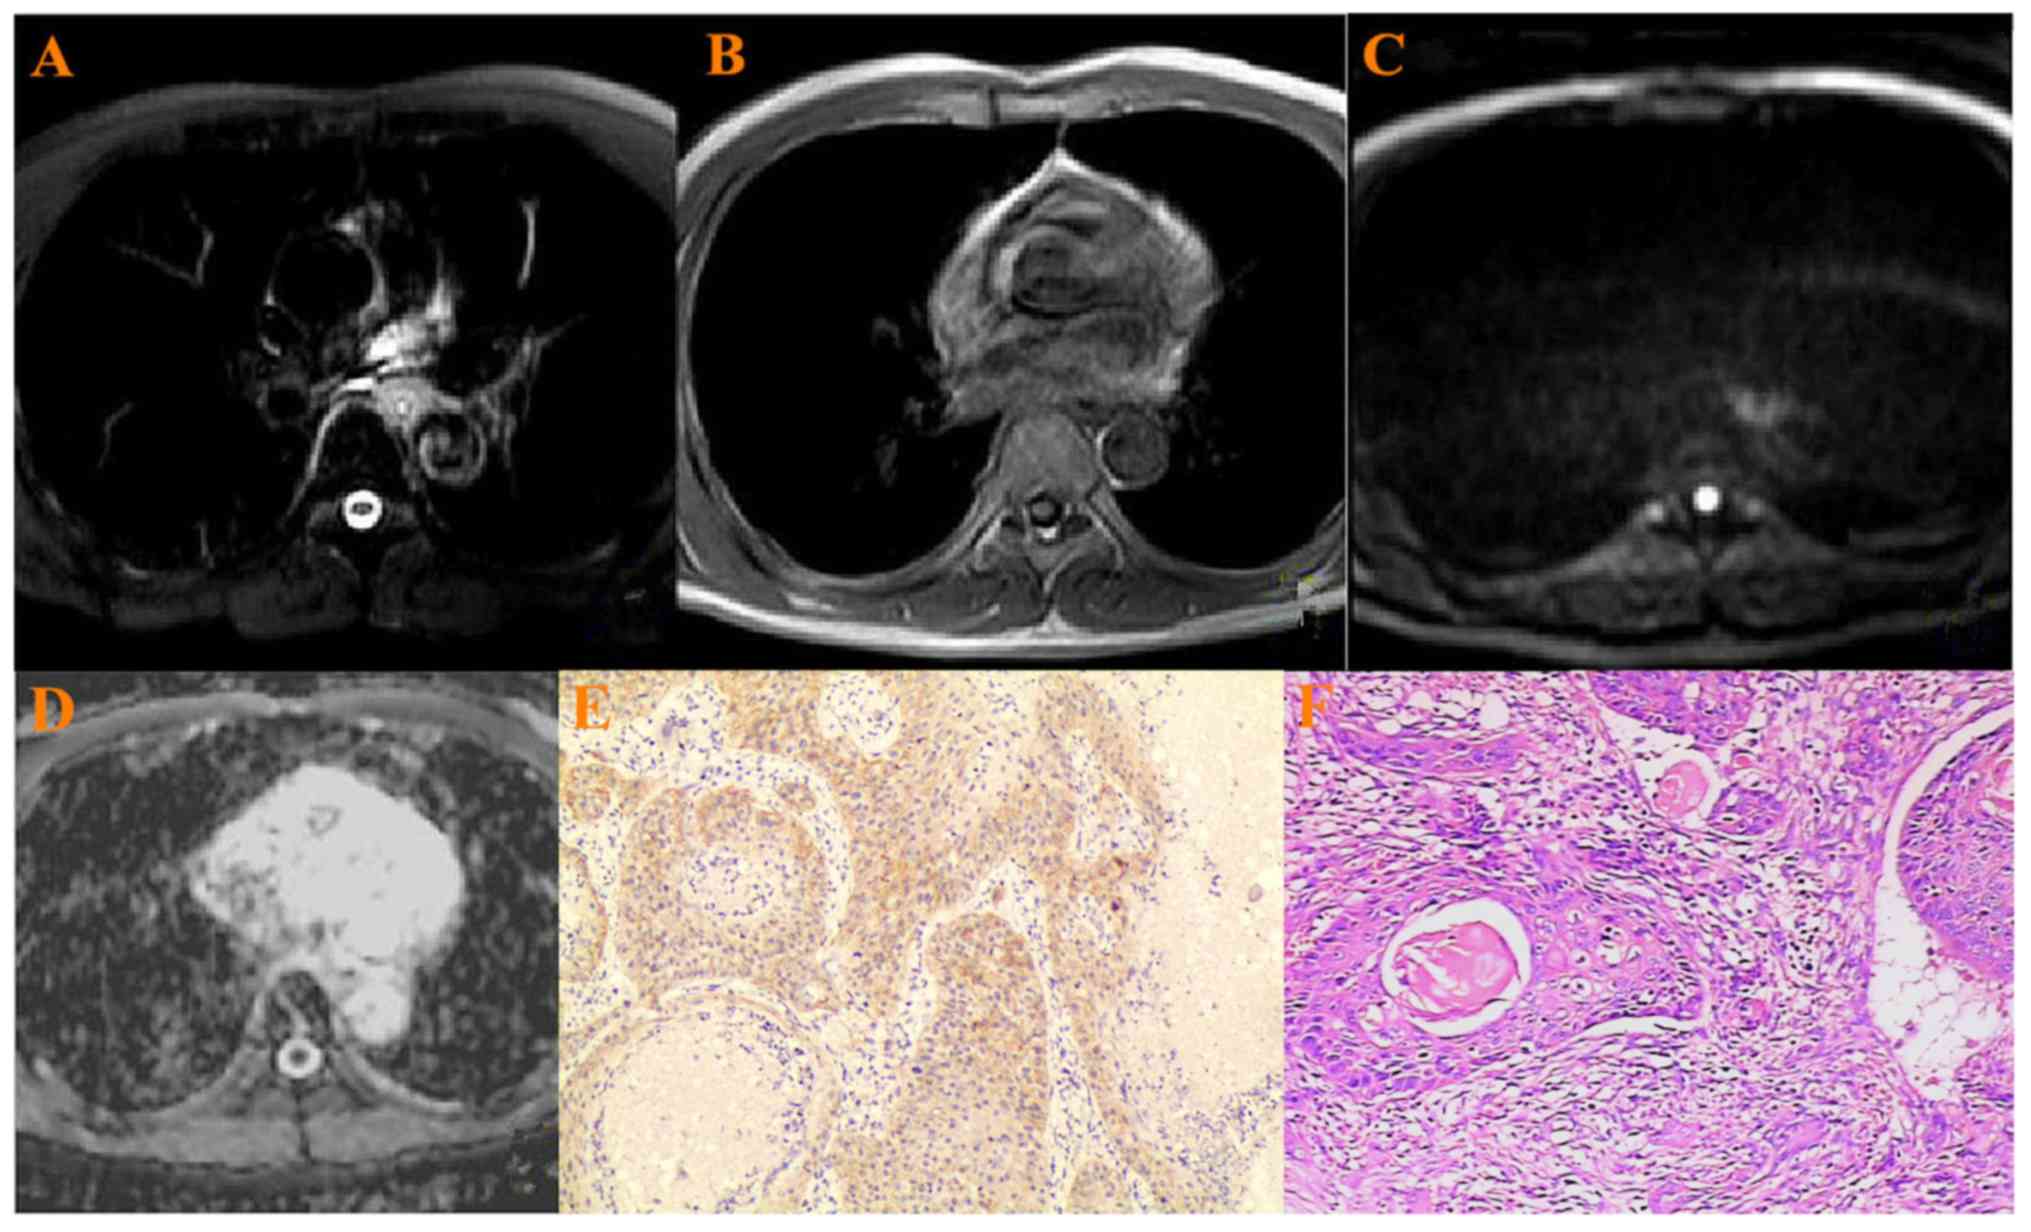

Figure 1.

A 75-year-old patient with ESCC in the mid-thoracic portion. (A) ESCC was hyperintense on T2-weighted image, (B) hypointense on T1-weighted image, (C) hyperintense on the DW-MRI (b=800 s/mm2) (D) hypointense on ADC map. ADC value:1.62±0.35×10−3 mm2/s. (E) Low VEGF staining in cytoplasm of ESCC: Weak positive (+) (×200 magnification), (F) Histopathology: Well differentiated squamous cell carcinoma (×200 magnification). ESCC, esophageal squamous cell carcinoma; DW-MRI, diffusion weighted-magnetic resonance imaging; ADC, apparent diffusion coefficient; VEGF, vascular endothelial growth factor.